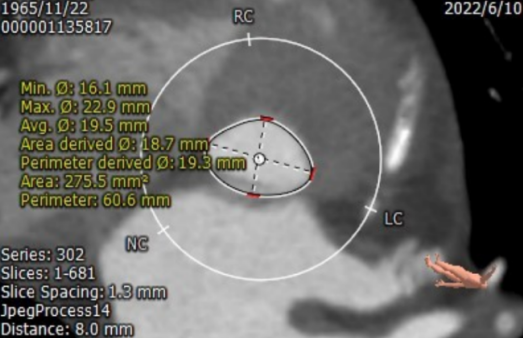

CT测量

主动脉瓣根部CT测量

瓣环周长:65.7mm;LVOT周长:59.2mm

瓣下2mm:20.4mm

瓣下4mm:19.0mm

瓣下6mm:18.8mm

瓣下8mm:19.5mm

• 患者瓣环周长65.7mm;平均直径21.2mm;LVOT周长59.2mm;平均直径19.0mm;